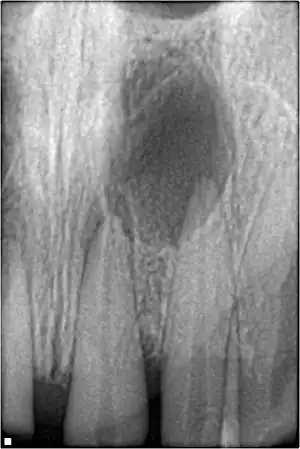

Xray showing peri-radicular radiolucency and bone loss caused by an odontogenic infection under the roots of two anterior teeth